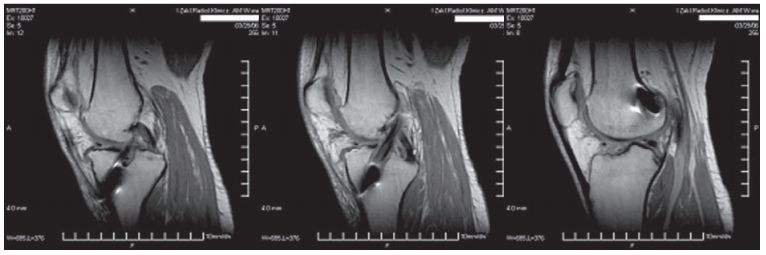

/ 8Badanie MR 12 tygodnie od zabiegu

Badanie MR 12 tygodnie od zabiegu (A) kanał piszczelowy, (B) część śródstawowa więzadła, (C) kanał udowy